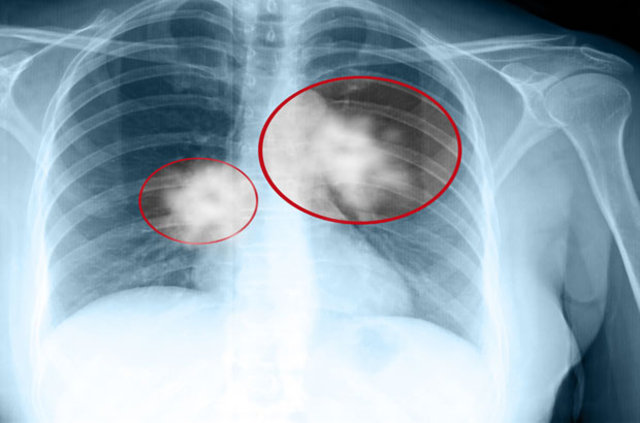

Akciğer kanserinin sinsi bir şekilde ilerleyerek ileri evrelerde ortaya çıkması, hastalığın erken evrede tanı almasının önemini ortaya çıkarıyor. Bu nedenle yapılan araştırmalar başta sigara kullananlar olmak üzere akciğer kanseri riski altında olanların 50 yaş ve üzerinde mutlaka tarama yaptırmasının gerekliliğine işaret ediyor. Bu taramalar sonucu erken evrede tanısı konulabilen akciğer kanseri, uygulanan tedavilerle tamamen ortadan kaldırılabilir.